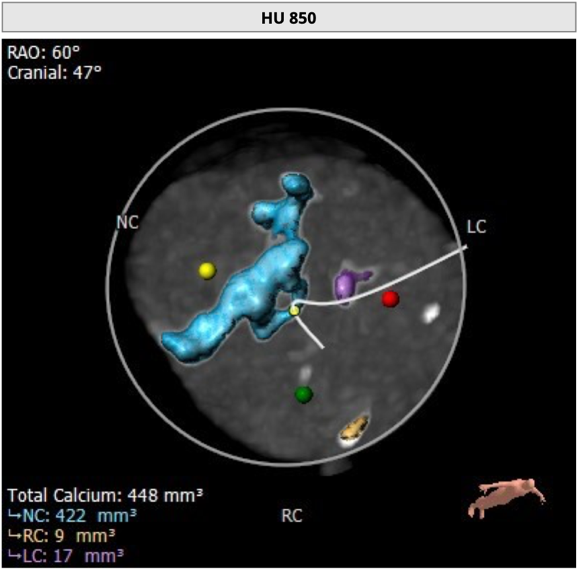

主动脉根部评估

CT 数据显示该患者为Type1型二叶式主动脉瓣

无冠瓣钙化严重,HU850:448mm³